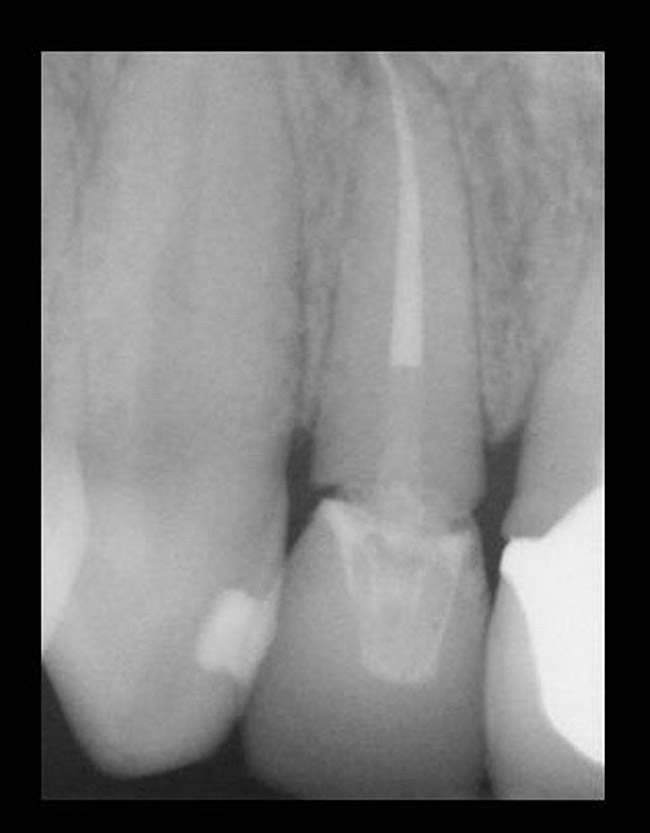

Figure 12  ENDODONTIC AND ESTHETIC PARAMETERS A tooth with a periapical radiolucency > 5 mm significantly decreases the success rate of endodontic therapy.

Figure 12

A tooth that is deemed structurally restorable and periodontally sound that requires endodontic therapy has an overall success rate of 90%. There are certain conditions that lower the success rate of which the clinician needs to be aware. According to the Toronto Study,34 a longitudinal study, a vital tooth requiring initial therapy will have a success rate of 93%. A non-vital tooth with a periapical radiolucency < 5 mm will have a 89% success rate.34 A non-vital tooth with periapical radiolucency > 5 mm will have a 74% success rate.34 Clearly, a tooth with periapical radiolucency > 5 mm significantly decreases the success rate of endodontic therapy (Figure 12).